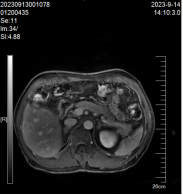

患者,林某某,男性,70岁,既往有乙肝病史,因体检发现肝脏占位入住我院肿瘤内科。入院后肝癌组团队医护立即完善相关检查,肝脏磁共振:肝Ⅵ段见团块状异常信号影,大小约为20mm×16mm×20mm,DWI呈高信号影,增强扫描呈不均匀强化(见图1)。甲胎蛋白(AFP) 1020.00IU/ml,AFP-L3甲胎蛋白异质体:31.20IU/ml,异常凝血酶原测定:341.00 mAU/mL。临床诊断为原发性肝癌,肝癌组卓曼云和张诚胜医生综合分析患者病情指出,患者诊断小肝癌明确,可选择微波消融或手术切除。患者家属考虑年纪大,不愿意手术治疗,遂在CT引导下行肝癌微波消融术。消融术中患者无手术出血,术后无明显不良反应,住院时间短,住院费用少,术后恢复快,1个月后复查肝脏MRI提示完全消融。目前患者定期复查未见复发。

消融前 消融中 消融后